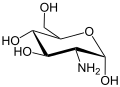

Glucosamine

Glucosamine(C6H13NO5) is an important component of cartilage, mucous membranes, and synovial fluid. It can be manufactured in the lab or extracted from the exoskeletons of lobsters, crabs, shrimp, and other sea creatures. It can be found in various forms like glucosamine sulfate,glucosamine hydrochloride and n-acetyl glucosamine. Efficacy of glucosamine is generally considered to be good and is supported by several studies.In the United States, glucosamine is not approved by the Food and Drug Administration for medical use in humans.[15] Since glucosamine is categorized as a dietary supplement in the US, safety and formulation are solely the responsibility of the manufacturer[16] . In most of Europe, glucosamine is approved as a medical drug and is sold in the form of glucosamine sulfate.[17]

Major side effects of all glucosamine salt are mild gastrointestinal problem such as constipation, diarrhea, cramping, gas, heartburn, and nausea. Glucosamine sulfate has been related to drowsiness and headache. The effects of glucosamine on nursing or pregnant women have not been studied well[18]. As glucosamine is an amino sugar and a prominent precursor for glucosaminoglycans, it may increase blood sugar levels. As glucosamine is often made from shellfish and the source of the product does not need the label, people who are allergic to seafood are advised to exercise caution as well.